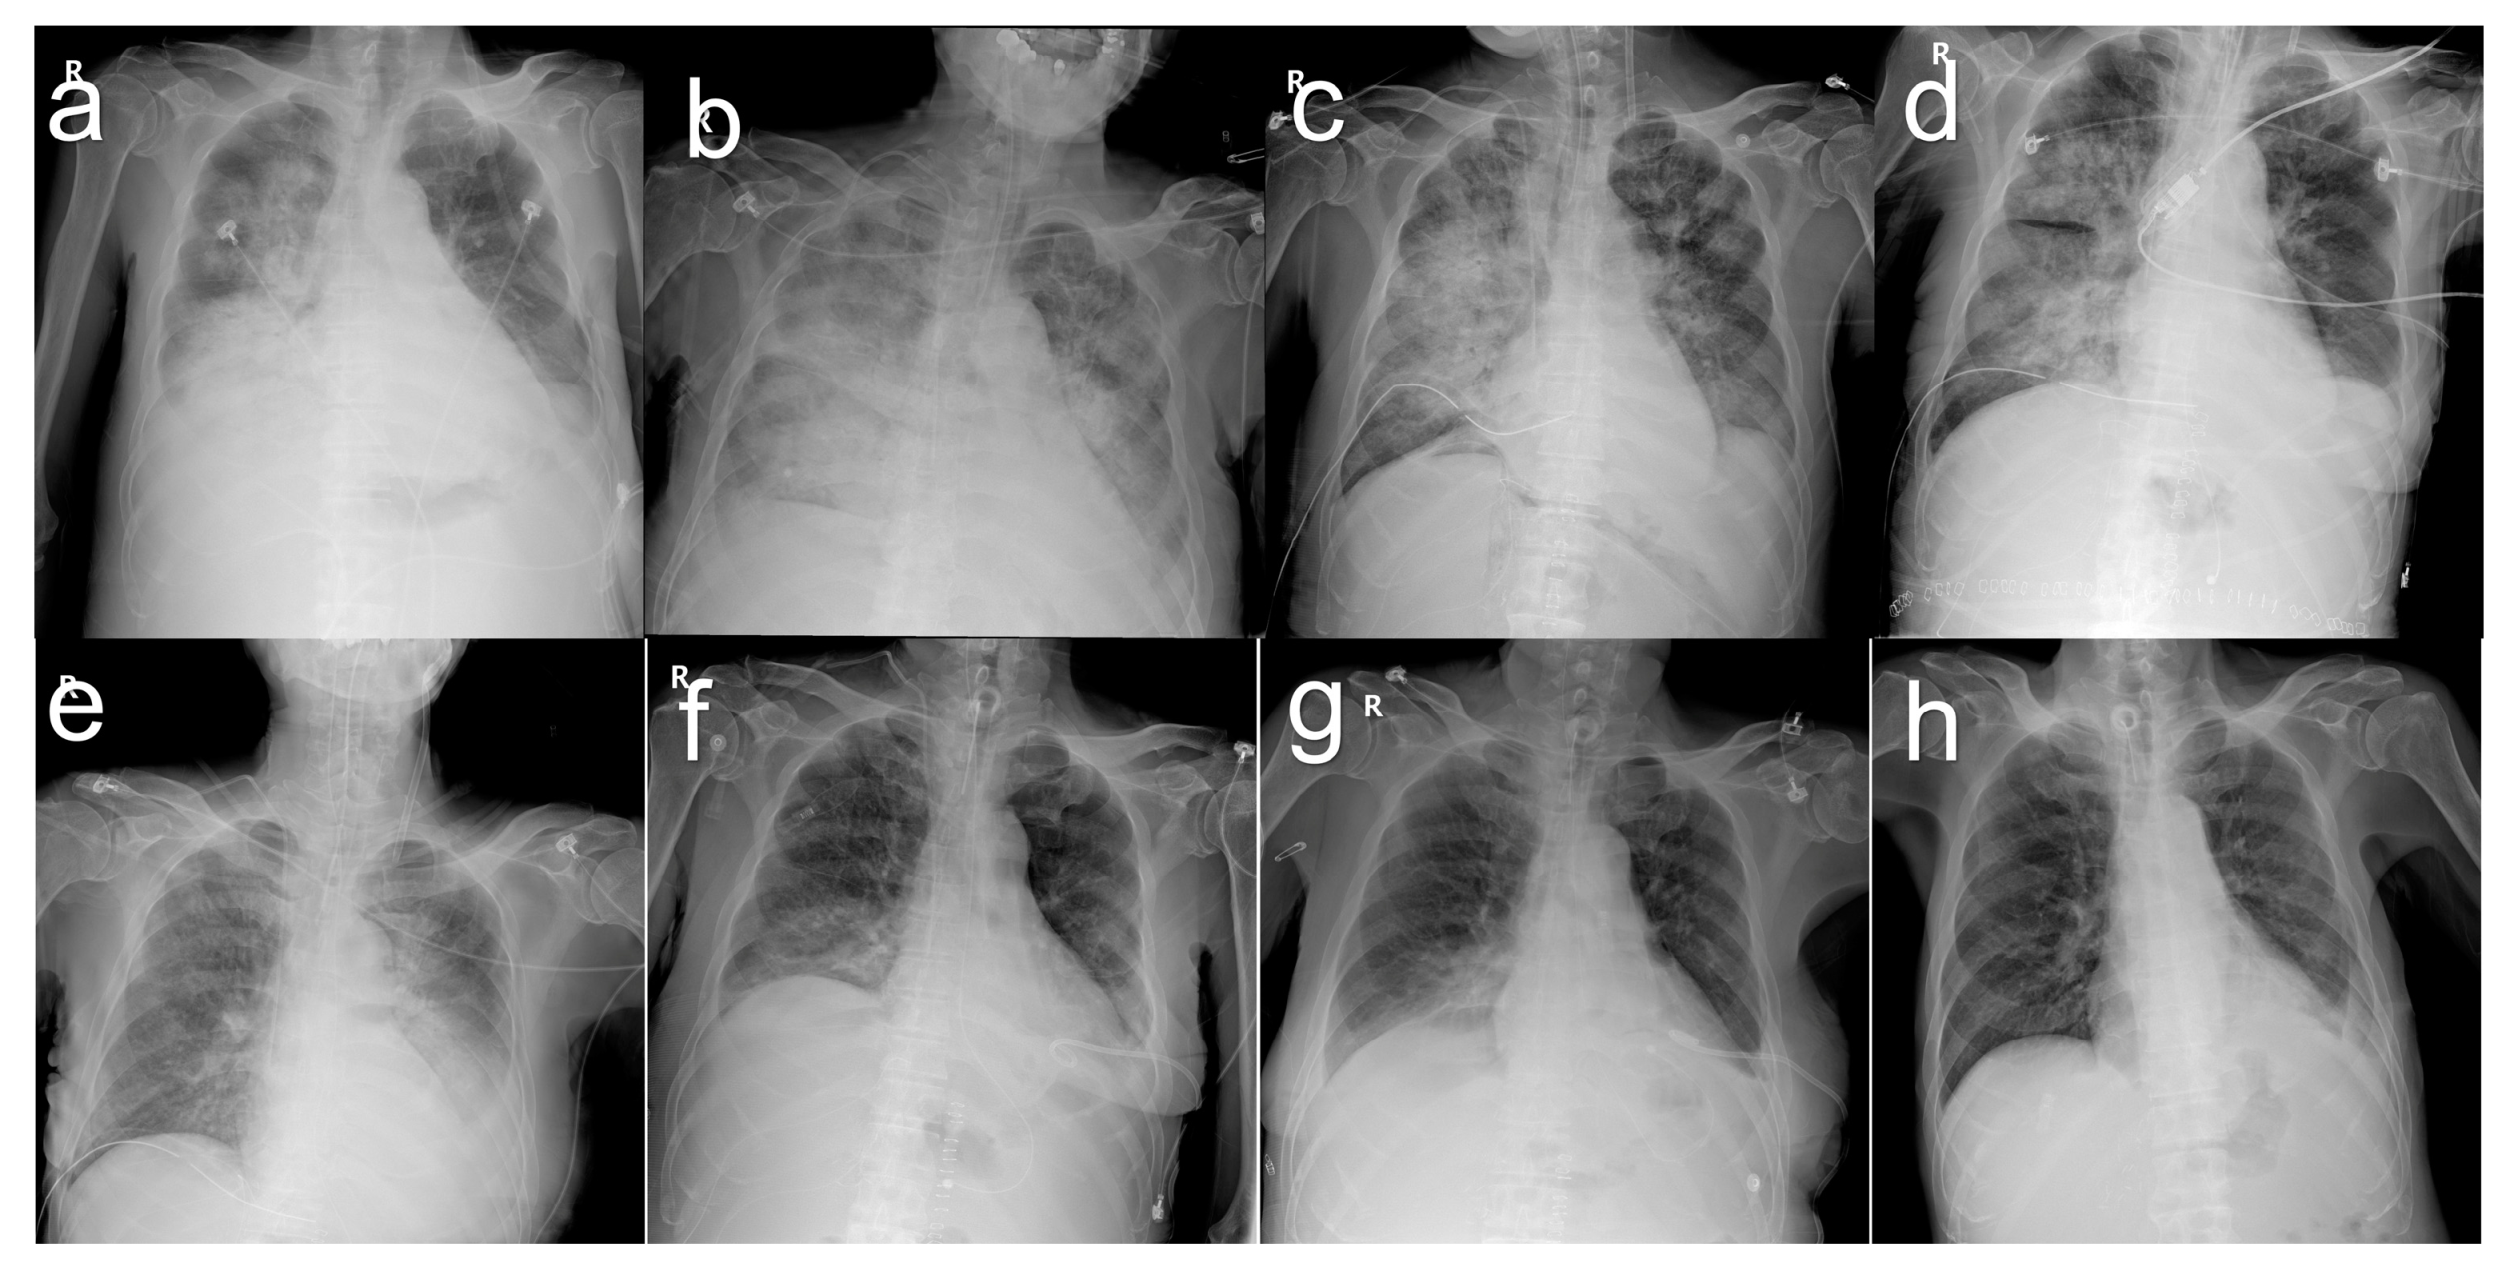

On 3 October 2014, the serum total bilirubin was 23.0 mg/dL. The abdominal CT scan revealed a parenchymal hematoma in the graft, with a stent visible in the bile duct and abundant ascites in the peritoneal cavity (Figure 3a). Additionally, the patient developed pneumonia (Figure 4a). The heart rate reached a maximum of 130 beats per minute and the body temperature rose to 38.0 °C. The respiration rate was over 30 breaths per min and the blood oxygen saturation dropped to 88%. His blood pressure dropped to 89/57 mm of mercury (mmHg). His mental status began to deteriorate. All the findings indicated shock due to sepsis. He was therefore transferred to the intensive care unit, intubated, and mechanically ventilated. Vasopressors were administered to treat low blood pressure. The cytomegalovirus (CMV) antigenemia assay showed positive results, so a preemptive intravenous injection of ganciclovir was initiated. Klebsiella pneumoniae was identified in the sputum culture and endotracheal aspirate culture, and antibiotics were initiated to treat pneumonia and sepsis. Fortunately, hemodialysis was not required; his renal function remained normal. His MELD score was 23, with a serum total bilirubin level of 29.1 mg/dL. In the state of liver failure, it was judged that pneumonia and sepsis were difficult to improve, so liver re-transplantation was seriously considered.

At the request of a preoperative risk evaluation, both the cardiologist and pulmonologist expressed skepticism regarding re-transplantation. Echocardiography revealed an ejection fraction of 41% and a mild systolic dysfunction of the dilated left ventricle. Successive chest X-rays showed worsening opacity on both sides of the lungs, suggesting a progressively increasing pattern of pulmonary edema. The ratio (P/F ratio) of arterial blood oxygen partial pressure (PaO2) to inhaled oxygen fraction (FiO2) was 93.5 mmHg, which was diagnosed as acute respiratory distress syndrome. However, blood pressure was stabilized and maintained above 100/60 mmHg even without vasopressors.

The two doctors were concerned that the risk of brain damage during the period of intraoperative hypoxia could be significant, and that the increased intraoperative fluid load and lung burden from blood transfusions could worsen the patient’s condition and even lead to death. There were also concerns about the possibility of continued respiratory failure after surgery and the possibility of prolonged treatment in the intensive care unit. Despite being informed of all the risks, the family desperately wanted a liver re-transplant. His twenty-year-old nephew volunteered to donate his right liver. His height was 176 cm and his weight was 72 kg, with a body mass index of 23.2. His blood type was A and Rh positive. The calculated MELD score just before re-transplantation was 26, with a serum total bilirubin level of 30.7 mg/dL. Arterial blood gas analysis just prior to re-transplantation showed a pH of 7.26, PaCO2 of 34.6 mmHg, PaO2 of 57.2 mmHg, and an oxygen saturation of 82.9%. A chest X-ray obtained on the morning of the re-transplant day showed extensive consolidation involving both lungs diffusely (Figure 4b).

After retransplant surgery, the patient was returned to the intensive care unit and continued mechanical ventilation while he was intubated. Ventilator weaning started on POD 9, and extubation was performed on POD 14. He was transferred to a general ward on POD 30. The serial chest X-ray findings showed improvement with an almost complete resolution of the abnormalities (Figure 4).

Figure 4. Series chest X-rays in the patient with pneumonia on pre-retransplant day 12 (a), preoperative day 0 (b), postoperative day 0 (c), postoperative day 4 (d), postoperative day 8 (e), postoperative day 16 (f), postoperative day 29 (g), and postoperative day 39 (h).